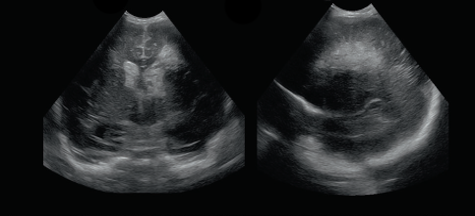

Neonatology PVHI Thalamus 1 Image